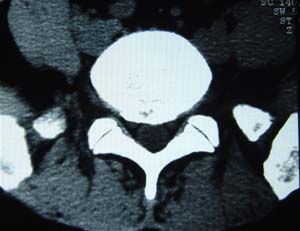

本人的片子,腰腿痛多年,时轻时重。请各位老师发表高见!

1.l4~5间盘膨出伴突出(中央型)

2.l5-s1后纵韧带钙化.